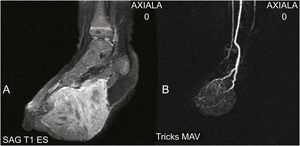

Os exames de ressonância magnética (RM) e a angiografia por ressonância magnética (ARM) revelaram massa sólida bem vascularizada, com envolvimento dos músculos subjacentes e extensão para a face anterior do pé. Havia realce difuso do contraste em toda a lesão, sem sinais de shunts arteriovenosos ou vasos tortuosos agrupados (nidus), afastando, assim, o diagnóstico de tumor vascular – entre eles, o hemangioendotelioma kaposiforme (fig. 2). Uma segunda biópsia foi realizada revelando tumor hipercelular fusiforme. A imuno‐histoquímica foi positiva para vimentina e negativa para CD31, CD34, fator VIII, desmina, MyoD1, miogenina, CD99 e EMA, possibilitando o diagnóstico de fibrossarcoma infantil congênito (FIC).